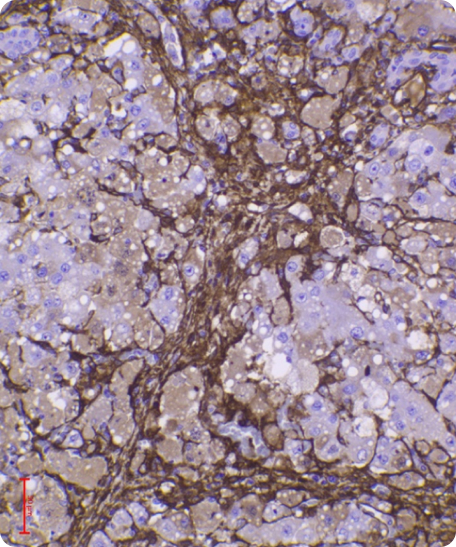

Animal trials are a crucial step in evaluating the safety and efficacy of novel medical products. In a rat model of severe liver failure, our combined stem cell & exosome therapy successfully repaired liver damage—an effect absent in the control group. While 40% of untreated subjects succumbed, 100% of those treated survived, highlighting both the regenerative and life-saving potential of our product.

This achievement was accepted as a poster presentation at the American Association for the Study of Liver Diseases conference (Nov 2024), with human trials set to begin in Q1 2025.

Liver damage with fibrosis

Before

After